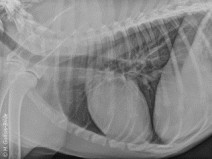

Le 4 mars 2017Aix-en-Provence (13100)Imagerie MédicaleG.E.I.M.199Après-midi Travaux pratiques de radiographie / TP2 l'abdomen

Le GEIM vous propose une séance de travaux pratiques de radiographies sur l'abdomen. Tous les aspects sont abordés sous la forme de TP de lecture de radiographies numériques sur station de travail Osirix sur Mac (3 vétérinaires maximum/ordinateur).